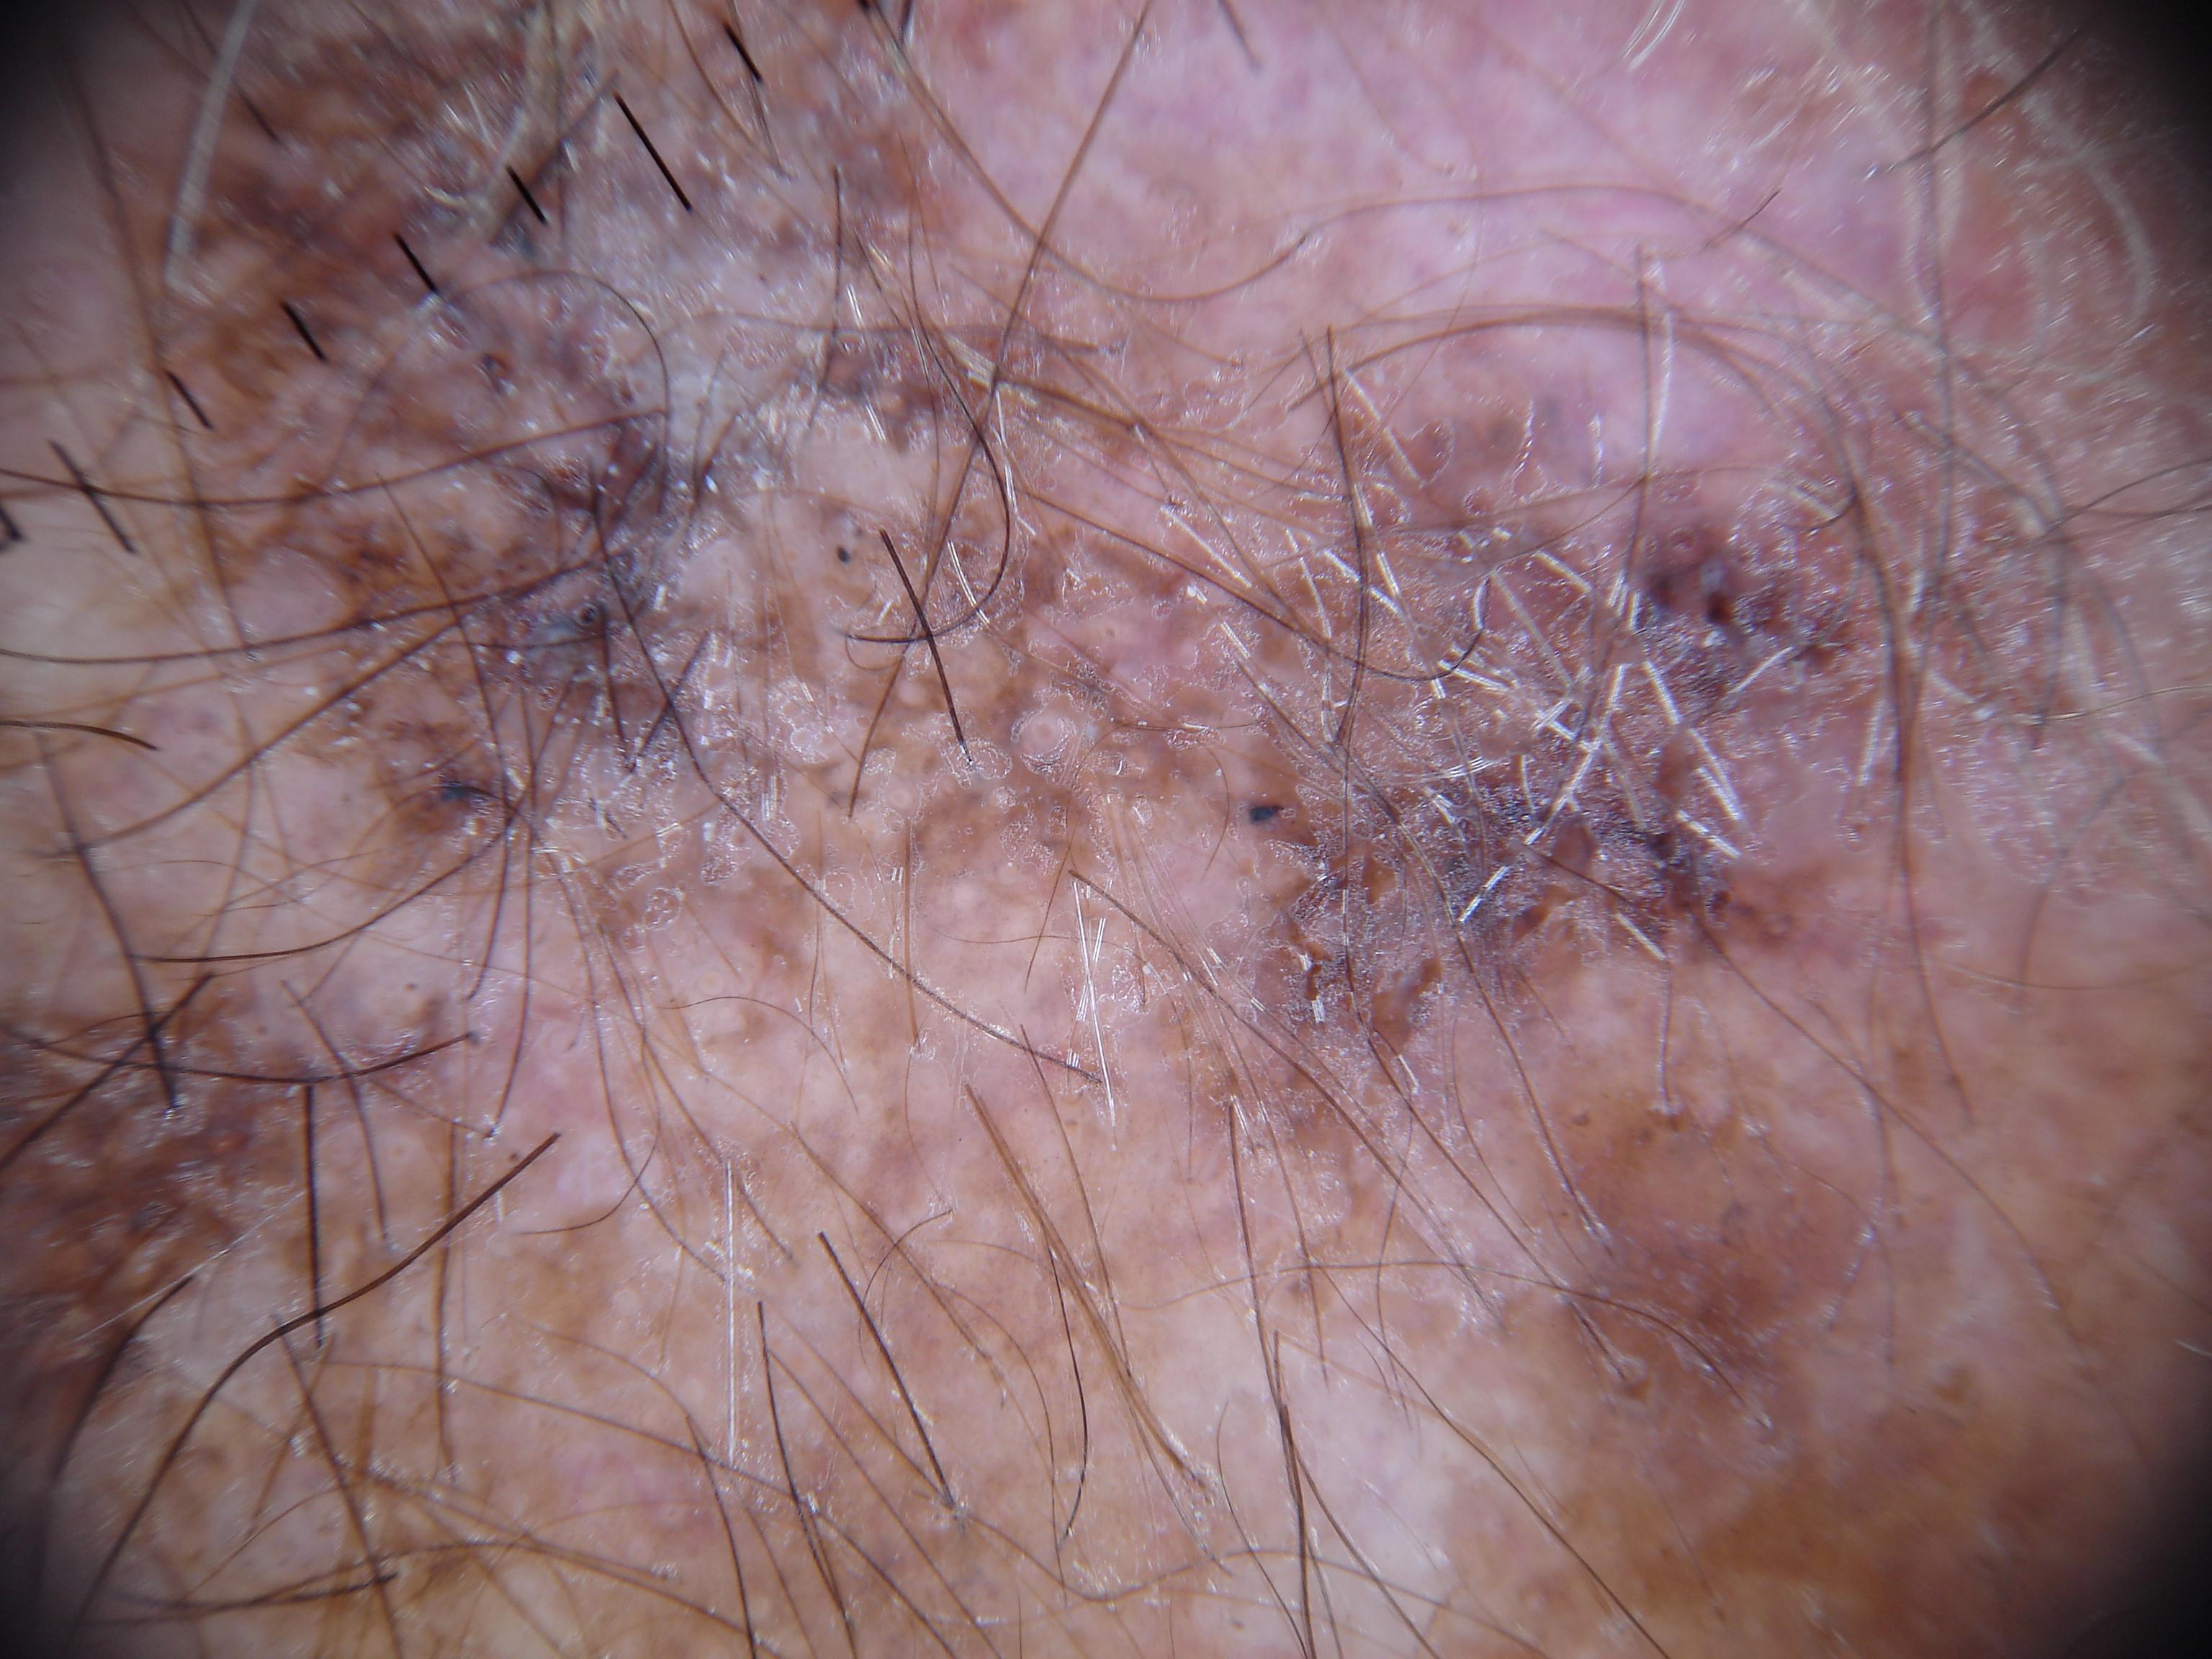

{

"age_approx": 85,

"anatom_site_general": "lower extremity",

"concomitant_biopsy": true,

"dermoscopic_type": "contact non-polarized",

"diagnosis_1": "Malignant",

"diagnosis_2": "Malignant melanocytic proliferations (Melanoma)",

"diagnosis_3": "Melanoma in situ",

"diagnosis_confirm_type": "histopathology",

"family_hx_mm": false,

"image_type": "dermoscopic",

"mel_thick_mm": "0.00",

"melanocytic": true,

"patient_id": "IP_9183698",

"personal_hx_mm": false,

"sex": "male"

}